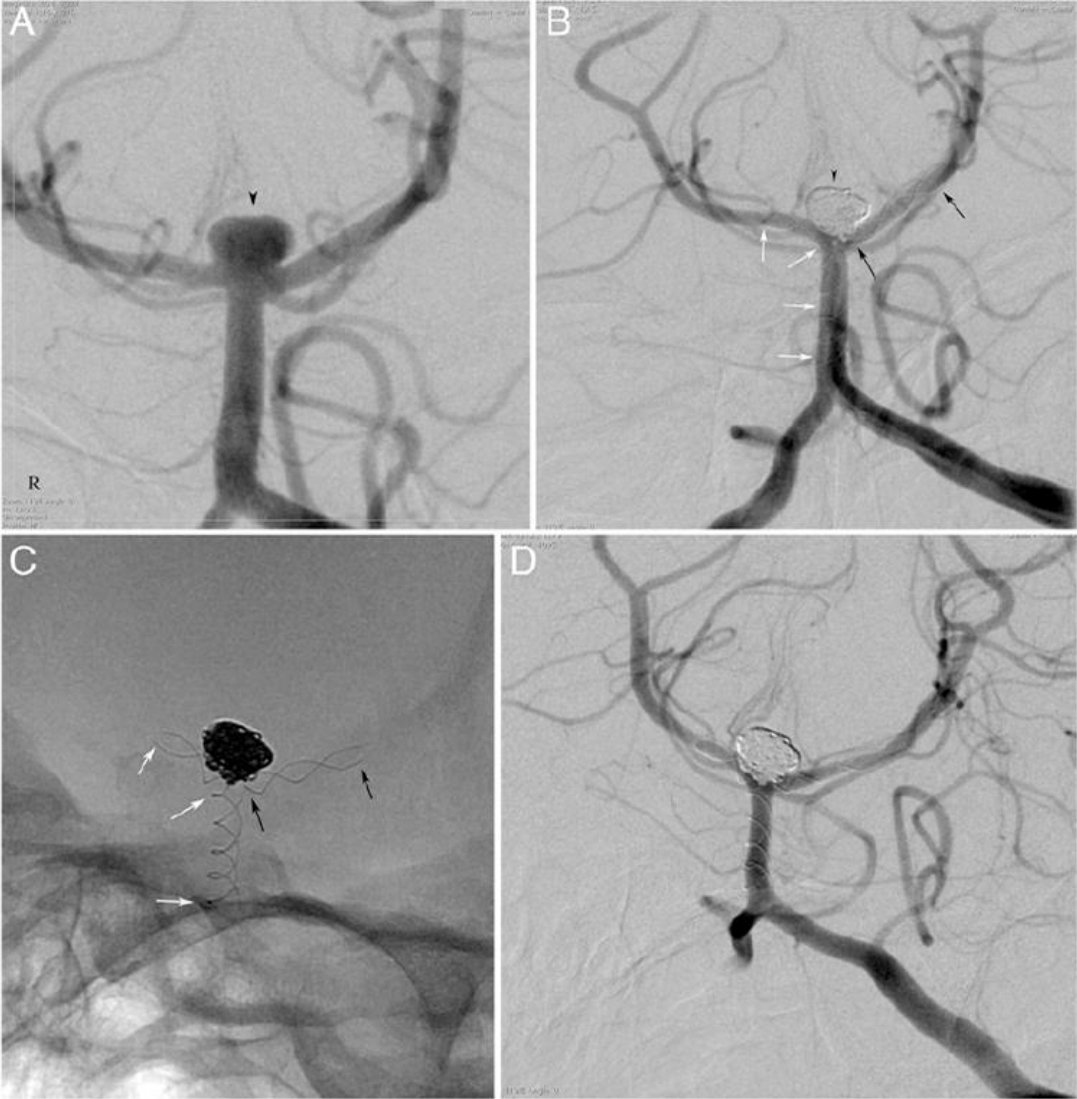

🧠اشعه بالصبغه

🧠اشعه تداخليه بالقسطرة للتشخيص والعلاج

🧠اشعه تداخليه بالقسطرة للتشخيص والعلاج

(مقطعيه بالصبغه/رنين مغناطيسي/اشعه صوتيه للرقبه/قسطرة تداخليه)

♦️قسطرة تداخليه لسحب الجلطه من الشرايين الرئيسيه ان وجدت

🧠عملية القسطرة التي يمكن إجراءها

♦️اول ٦ ساعات♦️من ظهور الأعراض